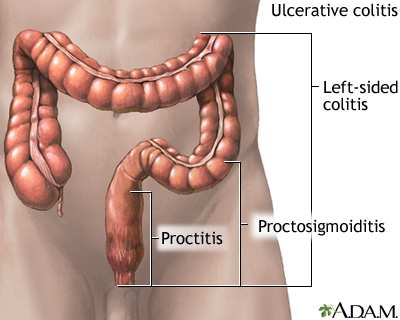

Crohn disease is a form of inflammatory bowel disease (IBD).

Ulcerative colitis is another form of IBD.